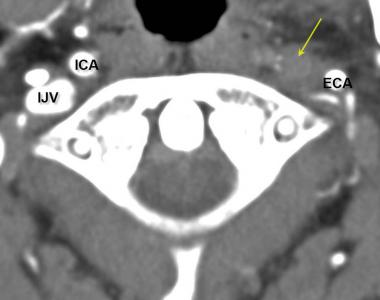

Occlusion of the internal jugular vein and vertebral artery

In patients who have a history of neck trauma or are suspected for atlas dysfunction/misalignment, compression of the internal jugular vein may be present. The internal jugular vein passes just anterior to the transverse process of the atlas vertebrae, and thus the C1’s transverse process doesn’t need to come very far forward in order to partially occlude it, partially blocking the cerebrovascular outlet.

If a patient has atlanto-occipital laxity, which is a somewhat taboo term but is surely reality for many patients, the atlas (C1) and axis (C2) may torsion between each other or in relation to the occiput. Atlantooccipital torsion (torsion between the cranium and C1) will cause the transverse process on one side to come forward, compressing the internal jugular vein along with the nervous structures coming out from the jugular foramen, such as the vagus nerve and the accessory nerve. With potential, due to its proximity, the internal carotid artery could also be partially occluded if there is severe atlanto-occipital torsion.

Fig. 5

Fig. 6

Furthermore, when the atlas twists on the occiput and/or on the C2, this will pull on the vertebral artery and may thus cause insufficiency as well. Therefore C1 laxity may compromise both the vertebral artery (due to increased distance between the transverse foramen of C1 and C2) as well as the internal jugular vein (due to forward translation of the C1’s transverse process). Evidence proving that vertebral artery occlusion is associated with migraines will be quoted in the scalene and thoracic outlet sub heading.

To properly measure the A-O joint, compare the position between the mastoid process of the skull and the transverse process of the atlas vertebrae. The C1 transverse process should bilaterally be situated directly beneath the mastoid process. Some osseous anomalies may occur, but not to significant extent. If the transverse process is too far forward, this may compress the internal jugular vein and pull on the vertebral artery, both contributing to migraines.